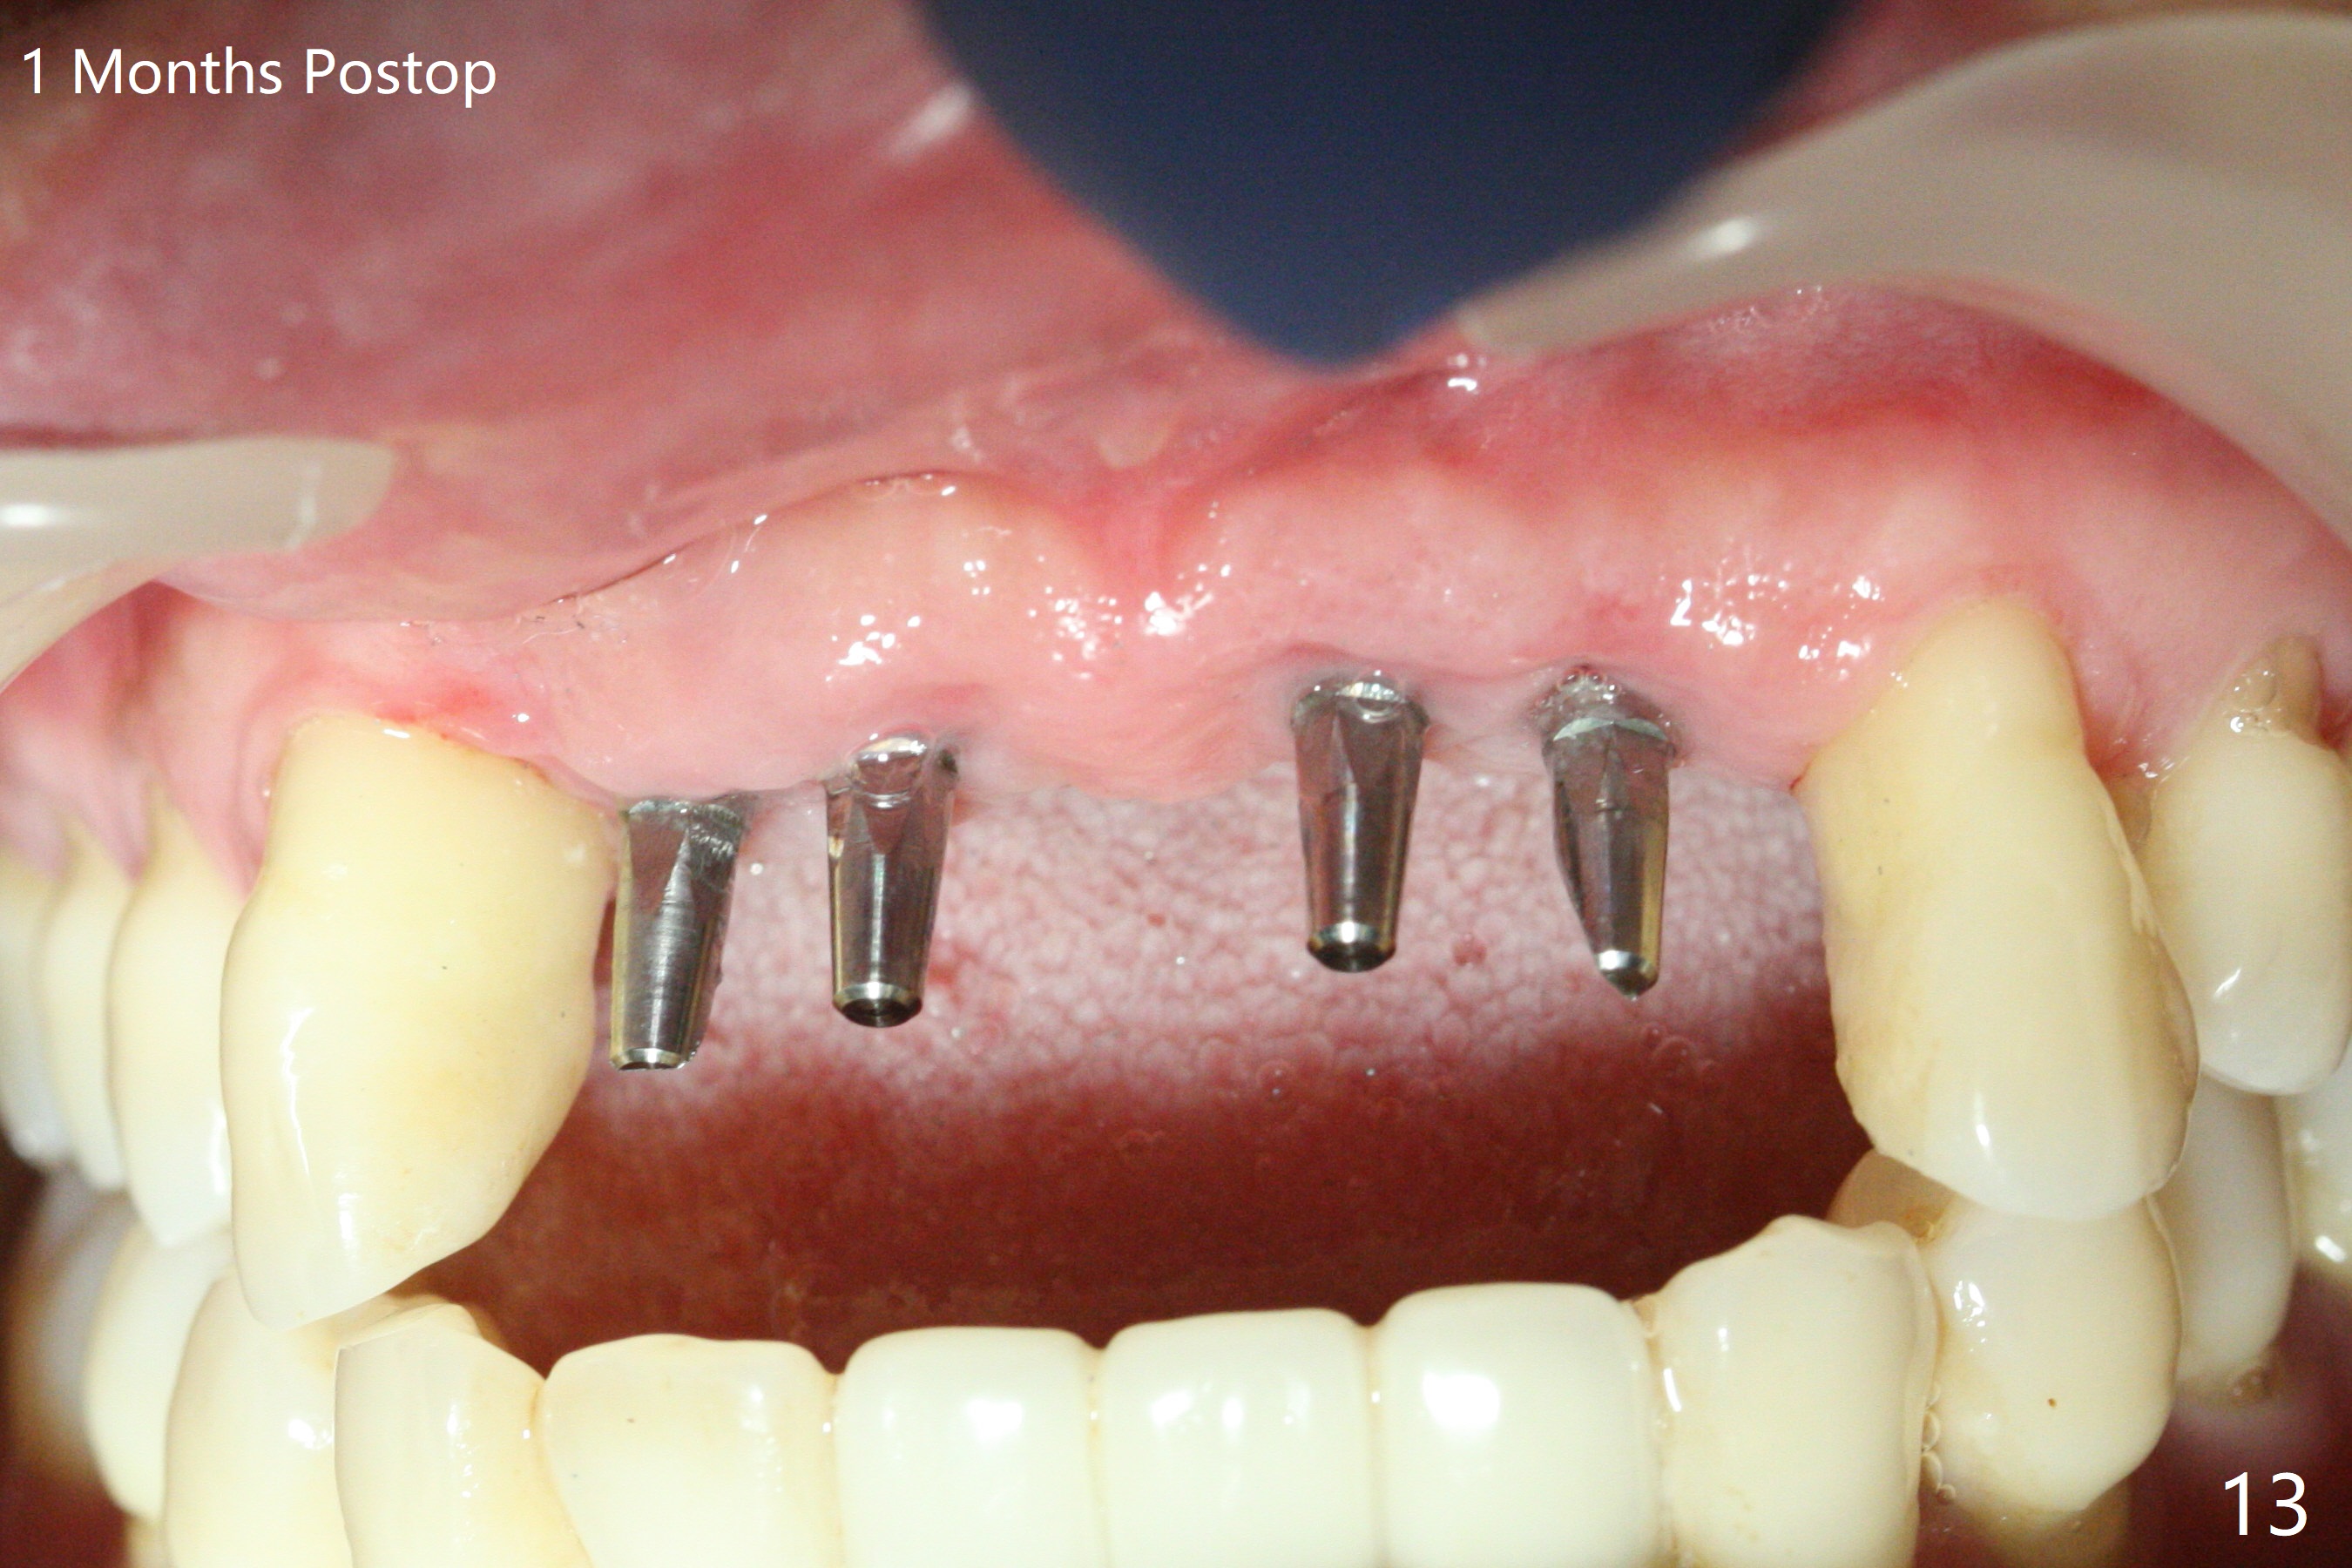

Although the ridge of the maxillary anterior ridge looks moderate in width (Fig.1), the bone is ~4 mm buccopalatally. Suction down surgical stent (Fig.2') made from the lab-fabricated provisional (Fig.2) will be used to check the position and trajectory of osteotomies. PAs taken after initial osteotomies (1.2 mm drill) show those at the central incisors tend to be mesial (close to the Incisive Canal *), while those at the lateral incisor sites distal (Fig.3,4). After adjustment, the position and trajectory of the osteotomies are acceptable (Fig.5,6). To reduce the chance of perforating the Incisive Canal (Fig.3,4 *), 2.5 mm 1-piece implants are inserted with >40 Ncm (Fig.7,8). After deep placement of the implants, Vanilla graft is placed at the crest (Fig.9,10 *). An immediate splinted provisional is fabricated from the suction down stent. The gingiva is healthy around the provisional (Fig.11) and the implants (Fig.12,13) 1 month postop. The provisional is adjusted monthly so that the interdental papillae can be elongated. No bone resorption is observed 6 months postop (Fig.14,15). Crowns are cemented 8 months postop (Fig.16-18). The keratinized gingiva appears to have formed the abutments 8 months postop immediately pre-cementation (Fig.19).